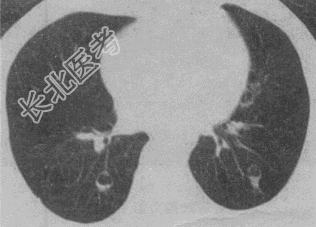

- 单项选择题患者女,23岁, 咳嗽咳痰反复发作,根据CT图像, 最可能的诊断是

A、支气管扩张并感染

B、多发肺气囊

C、多发性肺囊肿并感染

D、多发性肺脓肿

E、大叶性肺炎